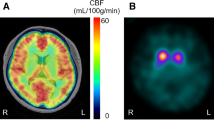

123I-MIBG scintigraphy

Patients were injected with 123I-MIBG (111 MBq) intravenously while in the upright position. Single-photon emission computed tomographic (SPECT) images were acquired 15 min after the injection and repeated 4 h later. Anterior and lateral planar images were acquired immediately after each SPECT acquisition. SPECT imaging was performed with a dual-head rotating gamma camera (Infinia Hawkeye, GE Medical Systems, Waukesha, WI, USA) equipped with a low-energy, general-purpose collimator. Images were acquired for 35 s each in 60 steps over a 360° orbit and were recorded at a digital resolution of 64 × 64 pixels. A 20% energy window centred on 159 keV was used. The heart/mediastinum count (H/M) ratio was determined from early and delayed anterior planar 123I-MIBG images, where H was the mean count/pixel in the left ventricle, and M was the mean count/pixel in the upper mediastinum. The delayed H/M ratio was used as an estimate of cardiac sympathetic activity. The normal value of the H/M ratio in our hospital from healthy volunteers is 2.00 in the late phase. This value was applied for the division of patients into two groups [20].

Statistical analysis

Patients were divided into two groups according to 123I-MIBG uptake: high-MIGB uptake and low-MIBG uptake (MIBGH and MIBGL). We applied a cut-off value of 2.00 for the heart/mediastinum (H/M) ratio calculated using MIBG scintigraphy [20]. The demographic characteristics of the participants are shown in Table 1.

The differences in grey matter volume between the MIBGL and MIBGH groups obtained via VBM analysis are depicted in Fig. 2. MIBGL patients demonstrated a significant reduction in grey matter volume in the right inferior frontal gyrus (pars opercularis, uncorrected p < 0.0001, K > 90) compared to MIBGH patients. There were no statistically significant differences in grey matter in any other regions of the brain between these two groups.

Grey matter volume reduction in the MIBGL and MIBGH groups observed by VBM analysis. Grey matter volume was significantly lower in the MIBGL group than in the MIBGH group at the inferior frontal gyrus (coordinates: x = 51.0, y = 19.5, z = 10.5; pars opercularis) on the right side (uncorrected p < 0.0001, K > 90)